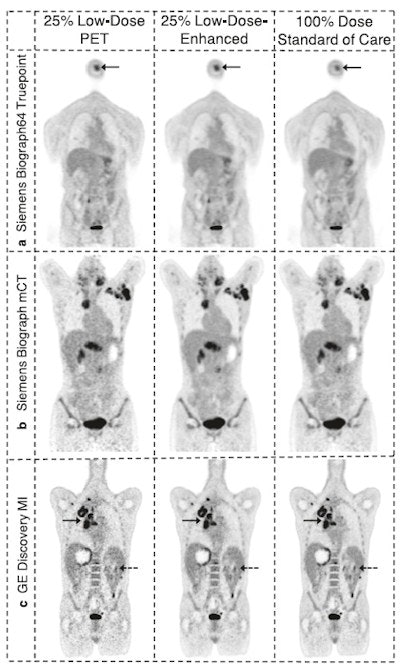

In this prospective study, a team of researchers evaluated the performance of an AI algorithm (SubtlePET, Subtle Medical) when applied to fourfold reduced-count whole-body PET in a realistic clinical environment with multiple blinded readers, institutions, and scanner types.

Three board-certified nuclear medicine physicians with seven, 12, and 22 years of experience at three separate academic institutions evaluated the efficacy of the low-count-enhanced PET scans. The readers evaluated two sets of PET scans per patient. One set consisted of the original 100% full-count PET scans ("standard") and one set consisted of 25% low-count PET scans enhanced using the AI software.

The readers detected a combined total of 491 hypermetabolic lesions in 92 total standard scans. The number of hypermetabolic lesions identified on the standard and low-count enhanced scans was not statistically different, the authors found.

The overall patient-level sensitivity and specificity for detecting lesions on the low-count-enhanced scan compared with the standard scan were 0.94 and 0.98. Interscan kappa agreement of 0.85 was comparable to intrareader (0.88) and pairwise interreader agreements (maximum of 0.72). SUV quantification was comparable in the reference regions and lesions and had high correlation.